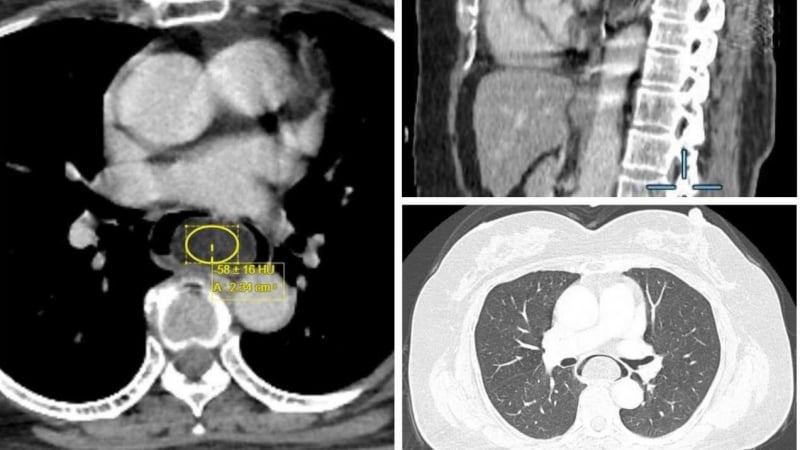

Người bệnh cho biết đã nuốt nghẹn kéo dài suốt 6 tháng. Qua thăm khám lâm sàng, các bác sĩ khoa Nội soi – Thăm dò chức năng, Bệnh viện K cho biết người bệnh có khối u thực quản. Khối u có cuống kích thước lớn, dưới niêm mạc, kích thước 16 x 3,5 x 3 cm.

Đây là khối u có kích thước khủng, thông thường các khối u dưới niêm mạc đường tiêu hóa có kích thước thường nhỏ hơn 3cm, và là “thủ phạm” gây ra cơn nuốt nghẹn của bệnh nhân.